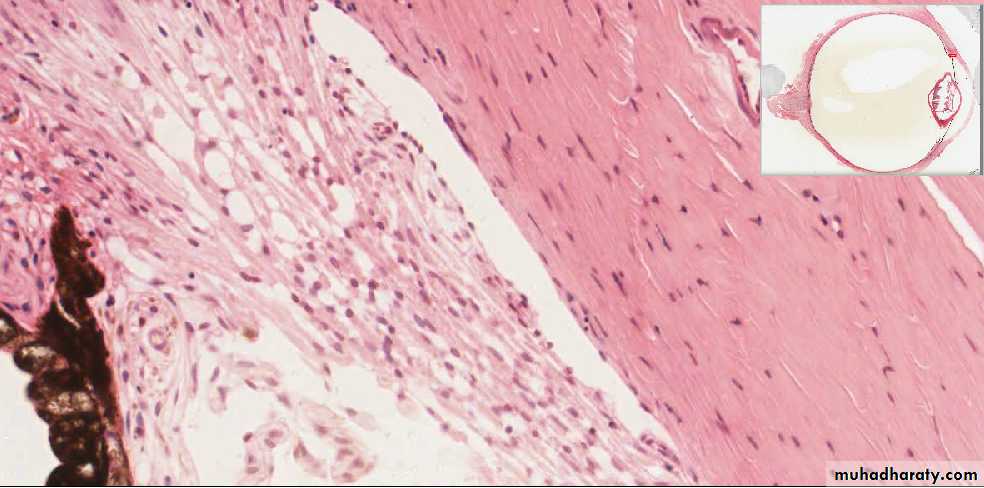

A section through the corneoscleral junction (limbus) showing (A) The canal of Schlemm, (B) The Ciliary processes, and (C) The Iris.

C

Sclera

Cornea

Canal of Schlemm

A higher magnification of the Corneoscleral junction showing the trabecular meshwork and the canal of SchlemmTrabecular meshwork